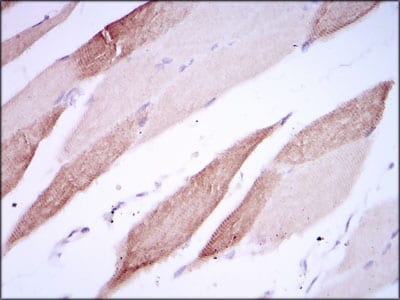

IHC 1/200 - 1/1000 Human,Mouse,Rat

AlCAM antibodies are essential tools for studying its biological functions and pathological roles. In research, they are widely used to detect AlCAM expression in cancer, where it is often overexpressed in tumors (e.g., melanoma, breast, and colorectal cancers) and linked to metastasis and poor prognosis. These antibodies enable techniques like immunohistochemistry, flow cytometry, and Western blotting to explore AlCAM's role in cell migration, invasion, and stem cell maintenance.